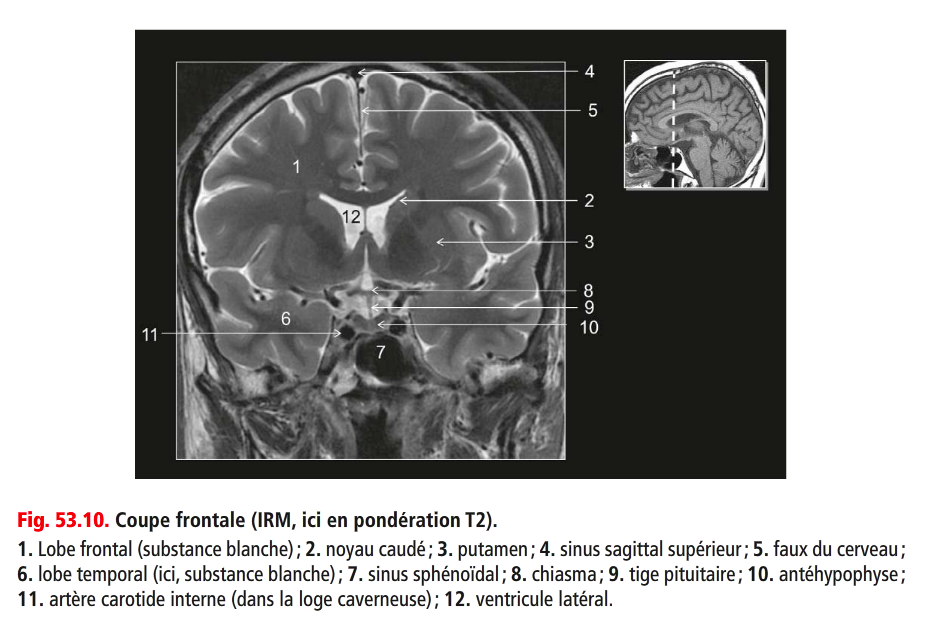

Coupe ? Légende ?